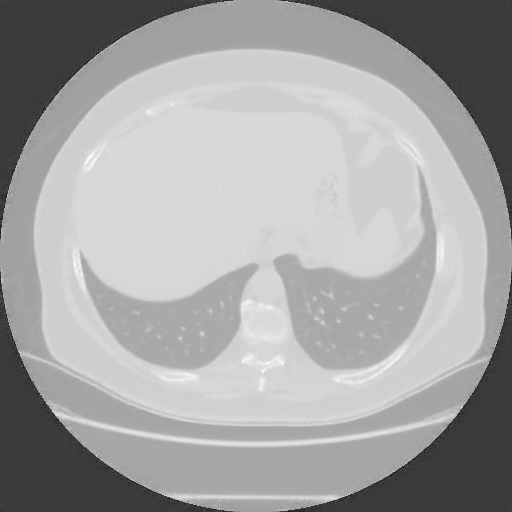

Original NATIVE CT scan (input)

No window - Raw intensity values

Lung window (WL -600, WW 1500 β†’ Low βˆ’1350, High +150)

Mediastinum window (WL 40, WW 400 β†’ Low βˆ’160, High +240)